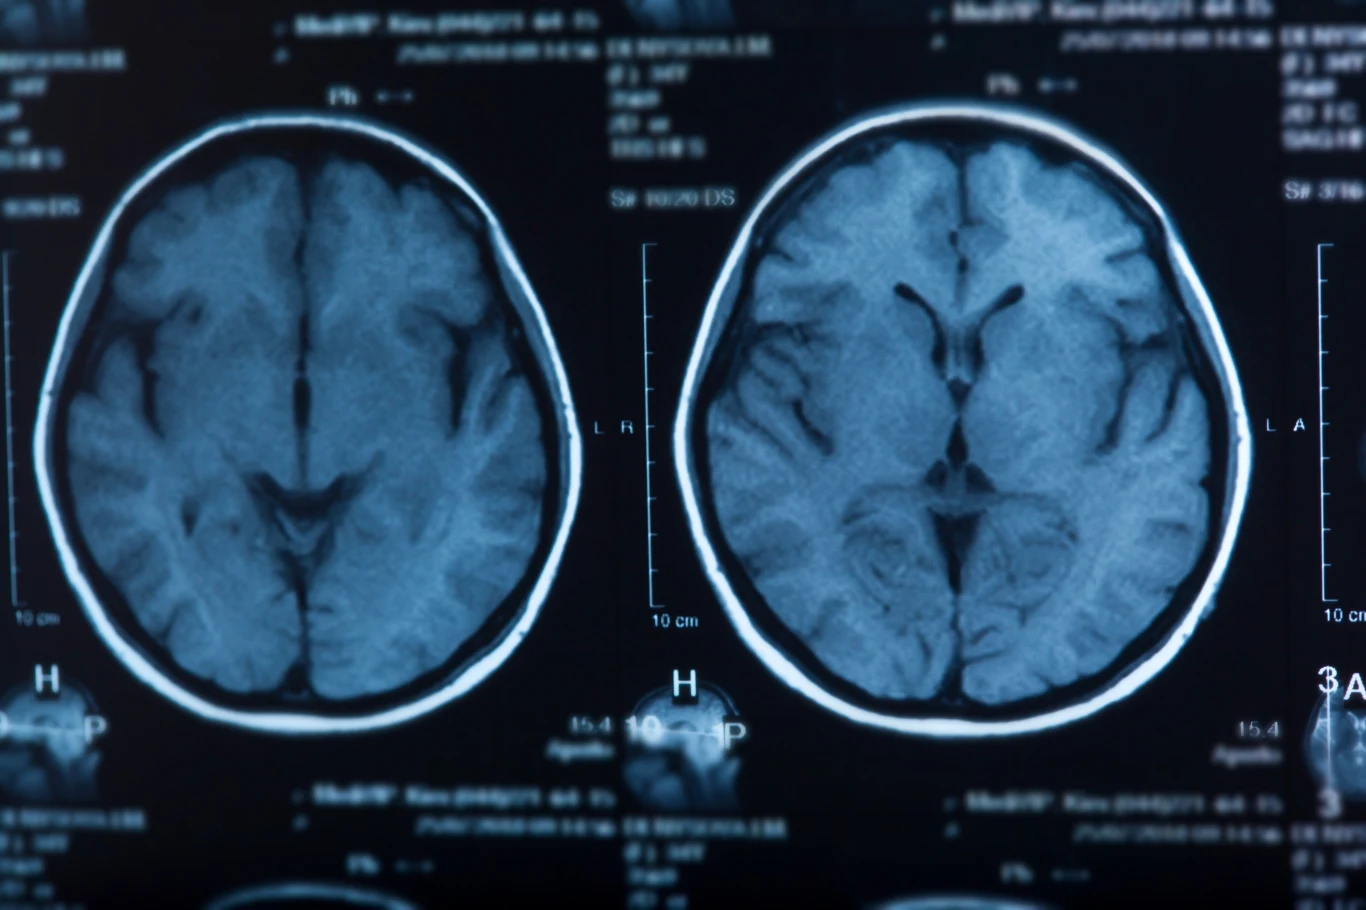

Naukowcy wciąż badają to, w jaki sposób zanieczyszczenie powietrza wpływa na nasze zdrowie i stale odkrywają nowe, niepokojące powiązania pomiędzy smogiem a różnymi schorzeniami. Powiązania te dotyczą nie tylko chorób płuc i serca, ale także funkcji mózgu, w tym między innymi ryzyka rozwoju demencji. Najnowsze badania, w tym praca naukowców ze Szkocji, wskazują na możliwy związek pomiędzy zanieczyszczeniem powietrza w dzieciństwie a ryzykiem rozwoju demencji w późniejszym życiu, w tym choroby Alzheimera.

Wyniki wskazują, że zanieczyszczenie powietrza w okresie prenatalnym i wczesnodziecięcym może zwiększać ryzyko rozwoju demencji w dorosłości. Badania wykazały, że dzieci, które dorastały w obszarach o wysokim poziomie zanieczyszczenia powietrza, miały większe szanse na rozwój choroby Alzheimera lub innych rodzajów demencji w późniejszych latach życia. Chociaż nie wszystkie wyniki były statystycznie istotne, to wśród badań pojawiły się wyraźne wzorce, które sugerują, że zanieczyszczenie powietrza w pierwszych latach życia może mieć długofalowy wpływ na zdrowie mózgu.

Zgodnie z badaniami Jutili, kluczowym okresem dla zdrowia mózgu może być czas prenatalny oraz wczesne dzieciństwo, kiedy rozwijający się organizm jest najbardziej wrażliwy na szkodliwe czynniki zewnętrzne. Zanieczyszczenie powietrza w tym okresie, szczególnie w postaci drobnych cząsteczek PM2.5 (cząstki stałe o średnicy mniejszej niż 2,5 mikrometra) oraz dwutlenku azotu (NO2), jest powiązane z wyższym ryzykiem rozwoju demencji w późniejszym życiu. Cząsteczki te są w stanie przedostać się do organizmu, a ich obecność w organizmach dzieci może prowadzić do uszkodzeń mózgu, które z biegiem lat mogą manifestować się jako zaburzenia poznawcze.